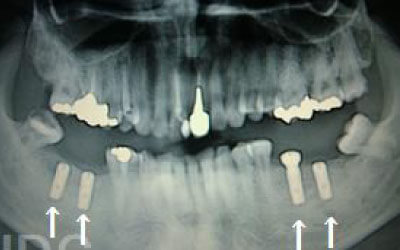

骨が薄い場合、そのままインプラントを行うのはお勧めできません。

ただし、事前に骨を増やす治療を行ったり、インプラントと同時に骨を増やす治療を行えば、インプラントは可能です。